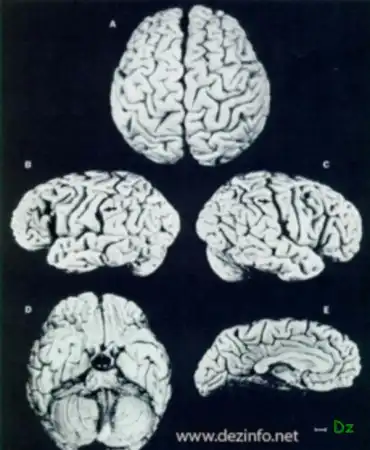

Мозг Эйнштейна

Что происходит когда мир теряет великого гения? Если его выдающийся мозг еще при жизни стал легендой, ему конечно же вскрывают череп, а мозг подвергают исследованиям. После смерти Эйнштейна в 1955 году его мозг был извлечен из черепной коробки патологоанатомом Томасом Харви, который и изготовил 240 срезов мозга для микроскопического исследования.